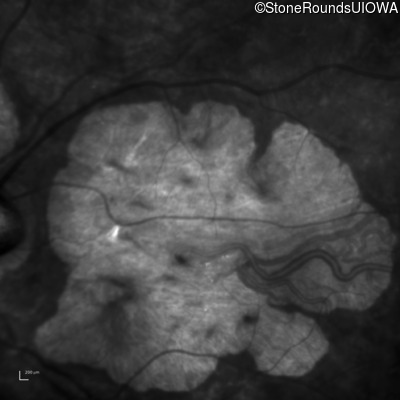

Infrared Fundus Photograph - Left - 20/150

Exemplar